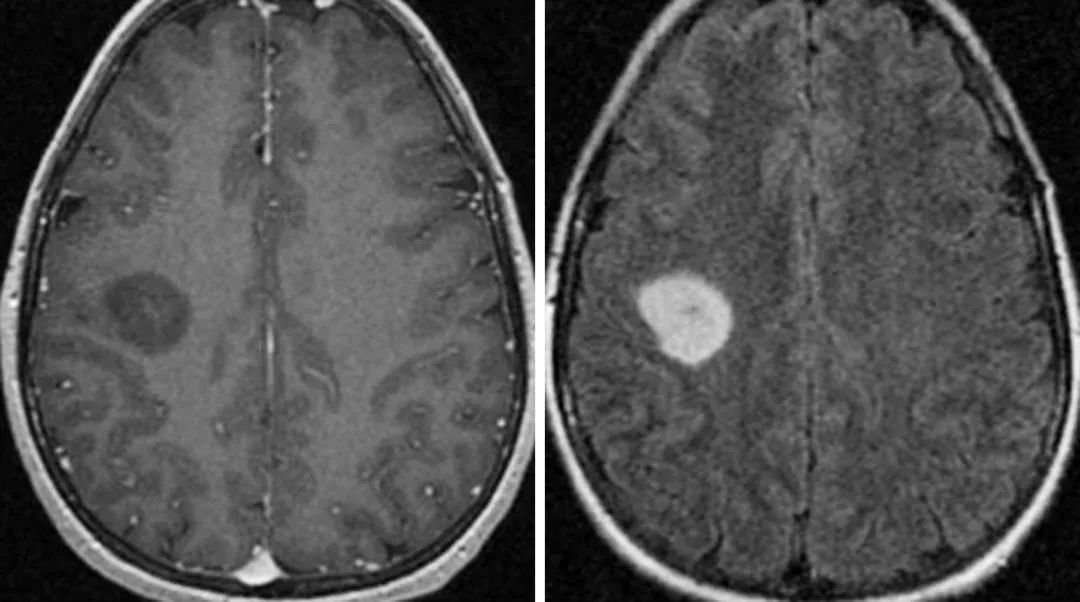

间变形星形细胞瘤属于WHO III 级。这种高级别的肿瘤特点是弥漫浸润生长,且该星形细胞肿瘤占脑胶质瘤的四分之一,预后较差。好发年龄为40-50岁。手术是间变性星形细胞瘤的首选治疗方法,目的是尽可能多地切除肿瘤组织,以减轻症状并延长生存期。由于肿瘤通常位于大脑深处或附近重要功能区,完全切除可能较困难。手术后常需进行放射治疗。

一般增强后扫描多为不规则环状强化,少数为结节状、斑片状强化。

MR平扫可见边界模糊异常信号灶,少部分边界清晰者可见类圆形肿块影,T1WI序列可见等/低信号,T2WI序列可见高信号,病灶内信号不均匀,可伴囊变信号影,病变周围少有水肿,占位效应轻;增强扫描后病灶强化不明显,或仅可见轻中度强度表现,以小片状、环状及结节状强化多见,伴囊变患者多可见非规则环形强化。